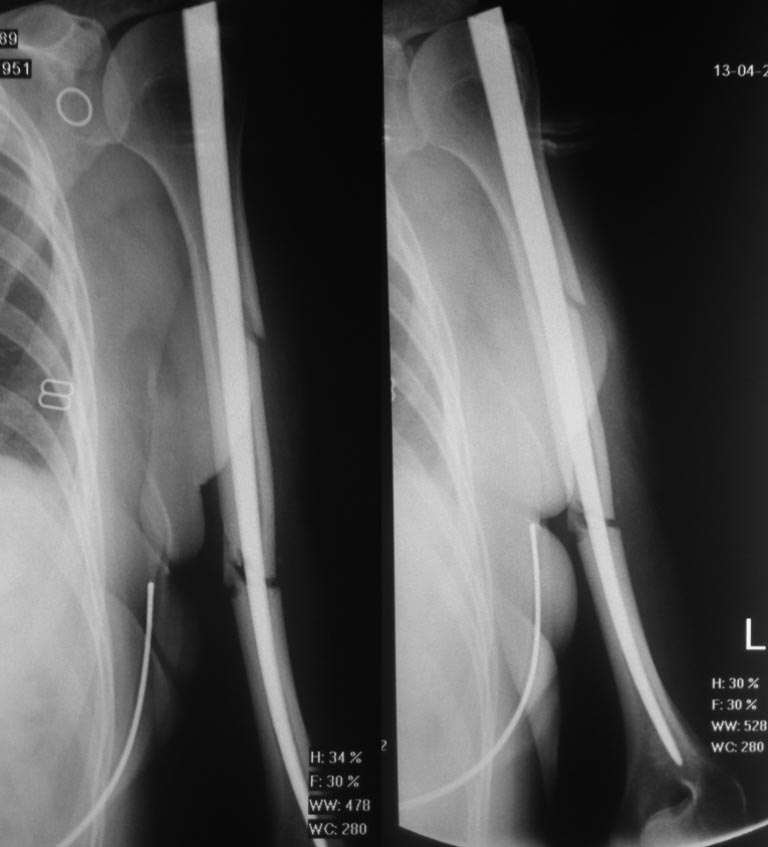

Спасибо вам большое за ответ! Вот снимки с первой операции - от 13.04.2016, с повторного приема через две недели после операции.

Касаемо остеомиелита: в январе 2017 года у пациентки определялся локальный отек и гиперемия в области перелома. По поводу этого она проходила лечение НПВС, и все, как я понял из её рассказа, свищей у неё не было. Так же, наши рентгенологи продублировали этот диагноз изучив её рентгенограммы.

Сделано-то было неплохо! Куда лучше, чем нынешний несостоятельный остеосинтез стержнем, практически не входящим в периферический отломок.

Единственное - использован "классический" вариант стержня Зверева-Ключевского с огромным прямоугольным проксимальным концом, торчащим в субакромиальное пространство, еще и введенным через сухожилие надостной мышцы. Но это отдельный вопрос, не имеющий отношения собственно к стабилизации перелома.

Вряд ли стоит сейчас возвращаться к этому же имплантату, но предполагаю, что поспешили и с диагнозом "псевдартроз" в срок 3 мес., и с реостеосинтезом. Который еще и сделан, мягко говоря, плохо.

Первичный остеосинтез имеет косвенное отношение к методу Зверева-Ключевского. В опубликованных работах уделено огромное значение месту введения стержня - в подбугорковой области метафиза, а не эпифиза. Стержень должен быть "несколько" иной формы. Несоблюдение всех правил заложенных авторами привело к дискридитации метода - раскалывание дистального фрагмента. Это видно по диастазу на уровне перелома (применено избыточное усилие) стержень изготовлен не по технологии авторов (видно по форме дистального и проксимального конца стержня). Хотели сделать хорошо, а ....